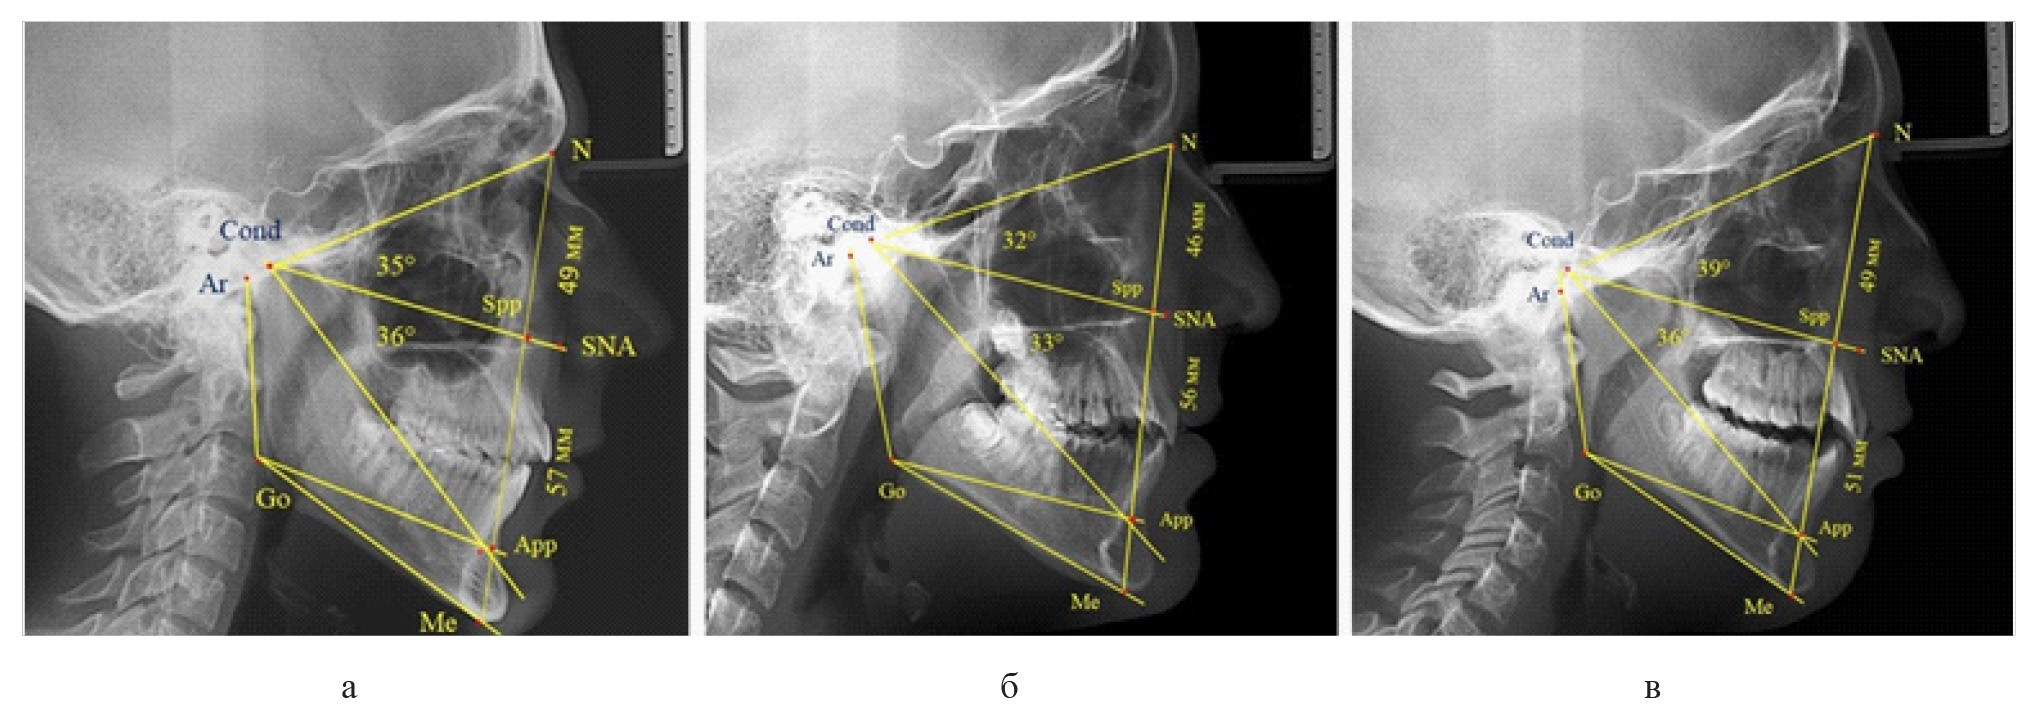

Среди пациентов с аномалиями челюстно-лицевой области в вертикальном направлении у 24 человек определялась глубокая резцовая окклюзия/дизокклюзия (рис. 5).

Рис. 5. Варианты ТРГ с оптимальными размерами носового отдела и оптимальными (а) и укороченными (б) размерами гнатической части лица

При этом только в двух случаях [(8,33 ± 5,64) %], параметры носового и гнатического отдела соответствовали норме. У 9 человек [(37,59 ± 9,88) %], при оптимальных параметрах назального отдела отмечалось уменьшение высоты гнатического отдела, вплоть до патологических показателей.

У людей с глубокой резцовой окклюзией нередко отмечалось изменение параметров носового отдела лица. Так, в 7 случаях было выявлено снижение параметров как носового, так и гнатического отделов лица. У 5 человек [(20,83 ± 8,28) %], отмечалось уменьшение носового отдела лица при оптимальных параметрах гнатического отдела.

В одном случае [(4,17 ± 4,08) %], определялось патологическое увеличение назального отдела лица при уменьшении гнатической его части. Некоторые варианты ТРГ пациентов с глубокой резцовой окклюзией представлены на рис. 6.

Рис. 6. Варианты ТРГ с уменьшенными размерами носового отдела и оптимальными (а) и укороченными (б) размерами гнатической части лица при глубокой резцовой окклюзии

Вертикальная резцовая дизокклюзия (открытый прикус) была проанализирована на 11 телерентгенограммах. При этом отмечались варианты как с оптимальными, так и увеличенными параметрами гнатической части лица при различных типах роста назального отдела, что представлено на рис. 7.

Рис. 7. Сравнительный анализ ТРГ при увеличенных размерах гнатической части с оптимальными (а), укороченными (б) и увеличенными (в) размерами носового отдела лица и вертикальной резцовой дизокклюзией